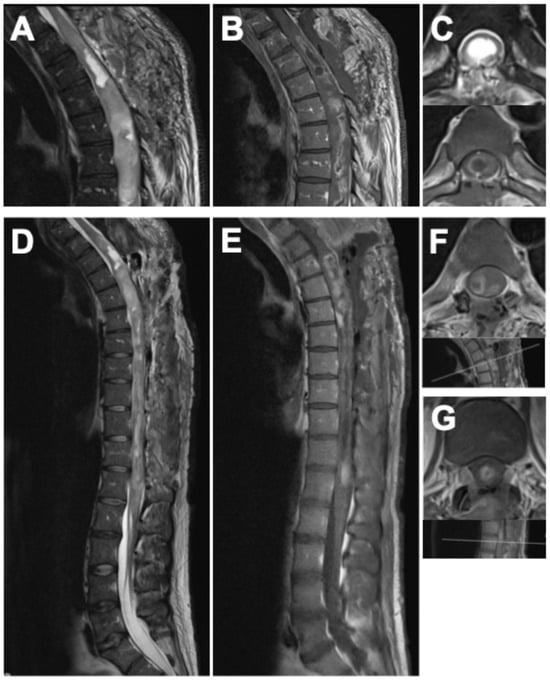

2.1.2. Imaging Findings

Whole-spine MRI demonstrated a heterogeneous, contrast-enhancing intramedullary tumor extending from T3 to the conus medullaris, associated with marked cord expansion and a multi-chambered syrinx. On T1-weighted sequences, the lesion appeared predominantly hyperintense with diffuse and partly nodular enhancement. Corresponding T2-weighted images revealed extensive hyperintense signal alterations with indistinct tumor–cord boundaries in several regions, as well as syrinx cavities spanning the thoracic and lumbar cord. Multifocal areas of hemorrhage were noted in the thoracic segments. In addition, a progressive T2-hyperintense signal without contrast enhancement was observed from C6 caudally, reflecting further myelon involvement at the cervical level. At the lumbar spine, an expansive intramedullary lesion centered at L1/2 with diffuse contrast uptake, and associated syrinx formation was identified, accompanied by additional hyperintense epidural formations, considered most likely to represent CSF loculations secondary to disturbed liquor circulation (Figure 1).

Figure 1. Preoperative imaging of the holocord astrocytoma. Cervical spine: (A) sagittal native T1-weighted MRI, (B) sagittal gadolinium-enhanced T1-weighted MRI, (C) sagittal native T2-weighted MRI, (D) axial gadolinium-enhanced T1-weighted MRI, and (E) axial native T2-weighted MRI. Thoracic spine: (F) sagittal native T1-weighted MRI, (G) sagittal gadolinium-enhanced T1-weighted MRI, (H) sagittal native T2-weighted MRI, (I) axial gadolinium-enhanced T1-weighted MRI, and (J) axial native T2-weighted MRI. Lumbar spine: (K) sagittal native T1-weighted MRI, (L) sagittal gadolinium-enhanced T1-weighted MRI, (M) sagittal native T2-weighted MRI, (N) axial gadolinium-enhanced T1-weighted MRI, and (O) axial native T2-weighted MRI.

As part of the preoperative staging, cranial MRI and CSF cytology were performed prior to the first operation and showed no evidence of intracranial tumor manifestation or malignant cells.